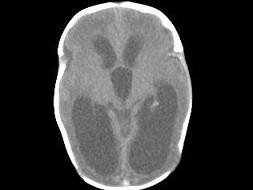

问题 1岁,女,头颅呈球状,颅骨透光试验阳性,请结合CT图片,选择最可能的诊断 ( )

选项 A、先天性脑积水 B、重度脑积水 C、慢性双侧性巨大硬膜下血肿 D、水瘤 E、脑严重缺血

答案 A